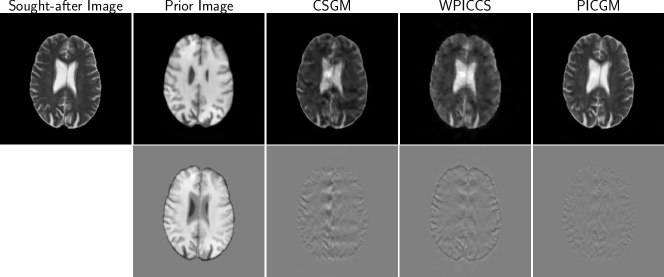

Figure 3: Sought-after image, prior image and image reconstruction results for an axial brain image, for 4-fold Cartesian undersampling and 20 dB SNR for the case where the sought-after and prior images are misaligned.

Additionally, it can be seen that the proposed approach is robust to misalignments in the sought-after and prior images such as unmatched slice locations. As shown in Fig. 3, PICGM is also able to recover the ventricles well, which is the region where the sought-after and prior images qualitatively differ the most. Quantitatively, Fig. 4 shows that the PICGM outperforms the other approaches examined even in the case of misaligned sought-after and prior images.